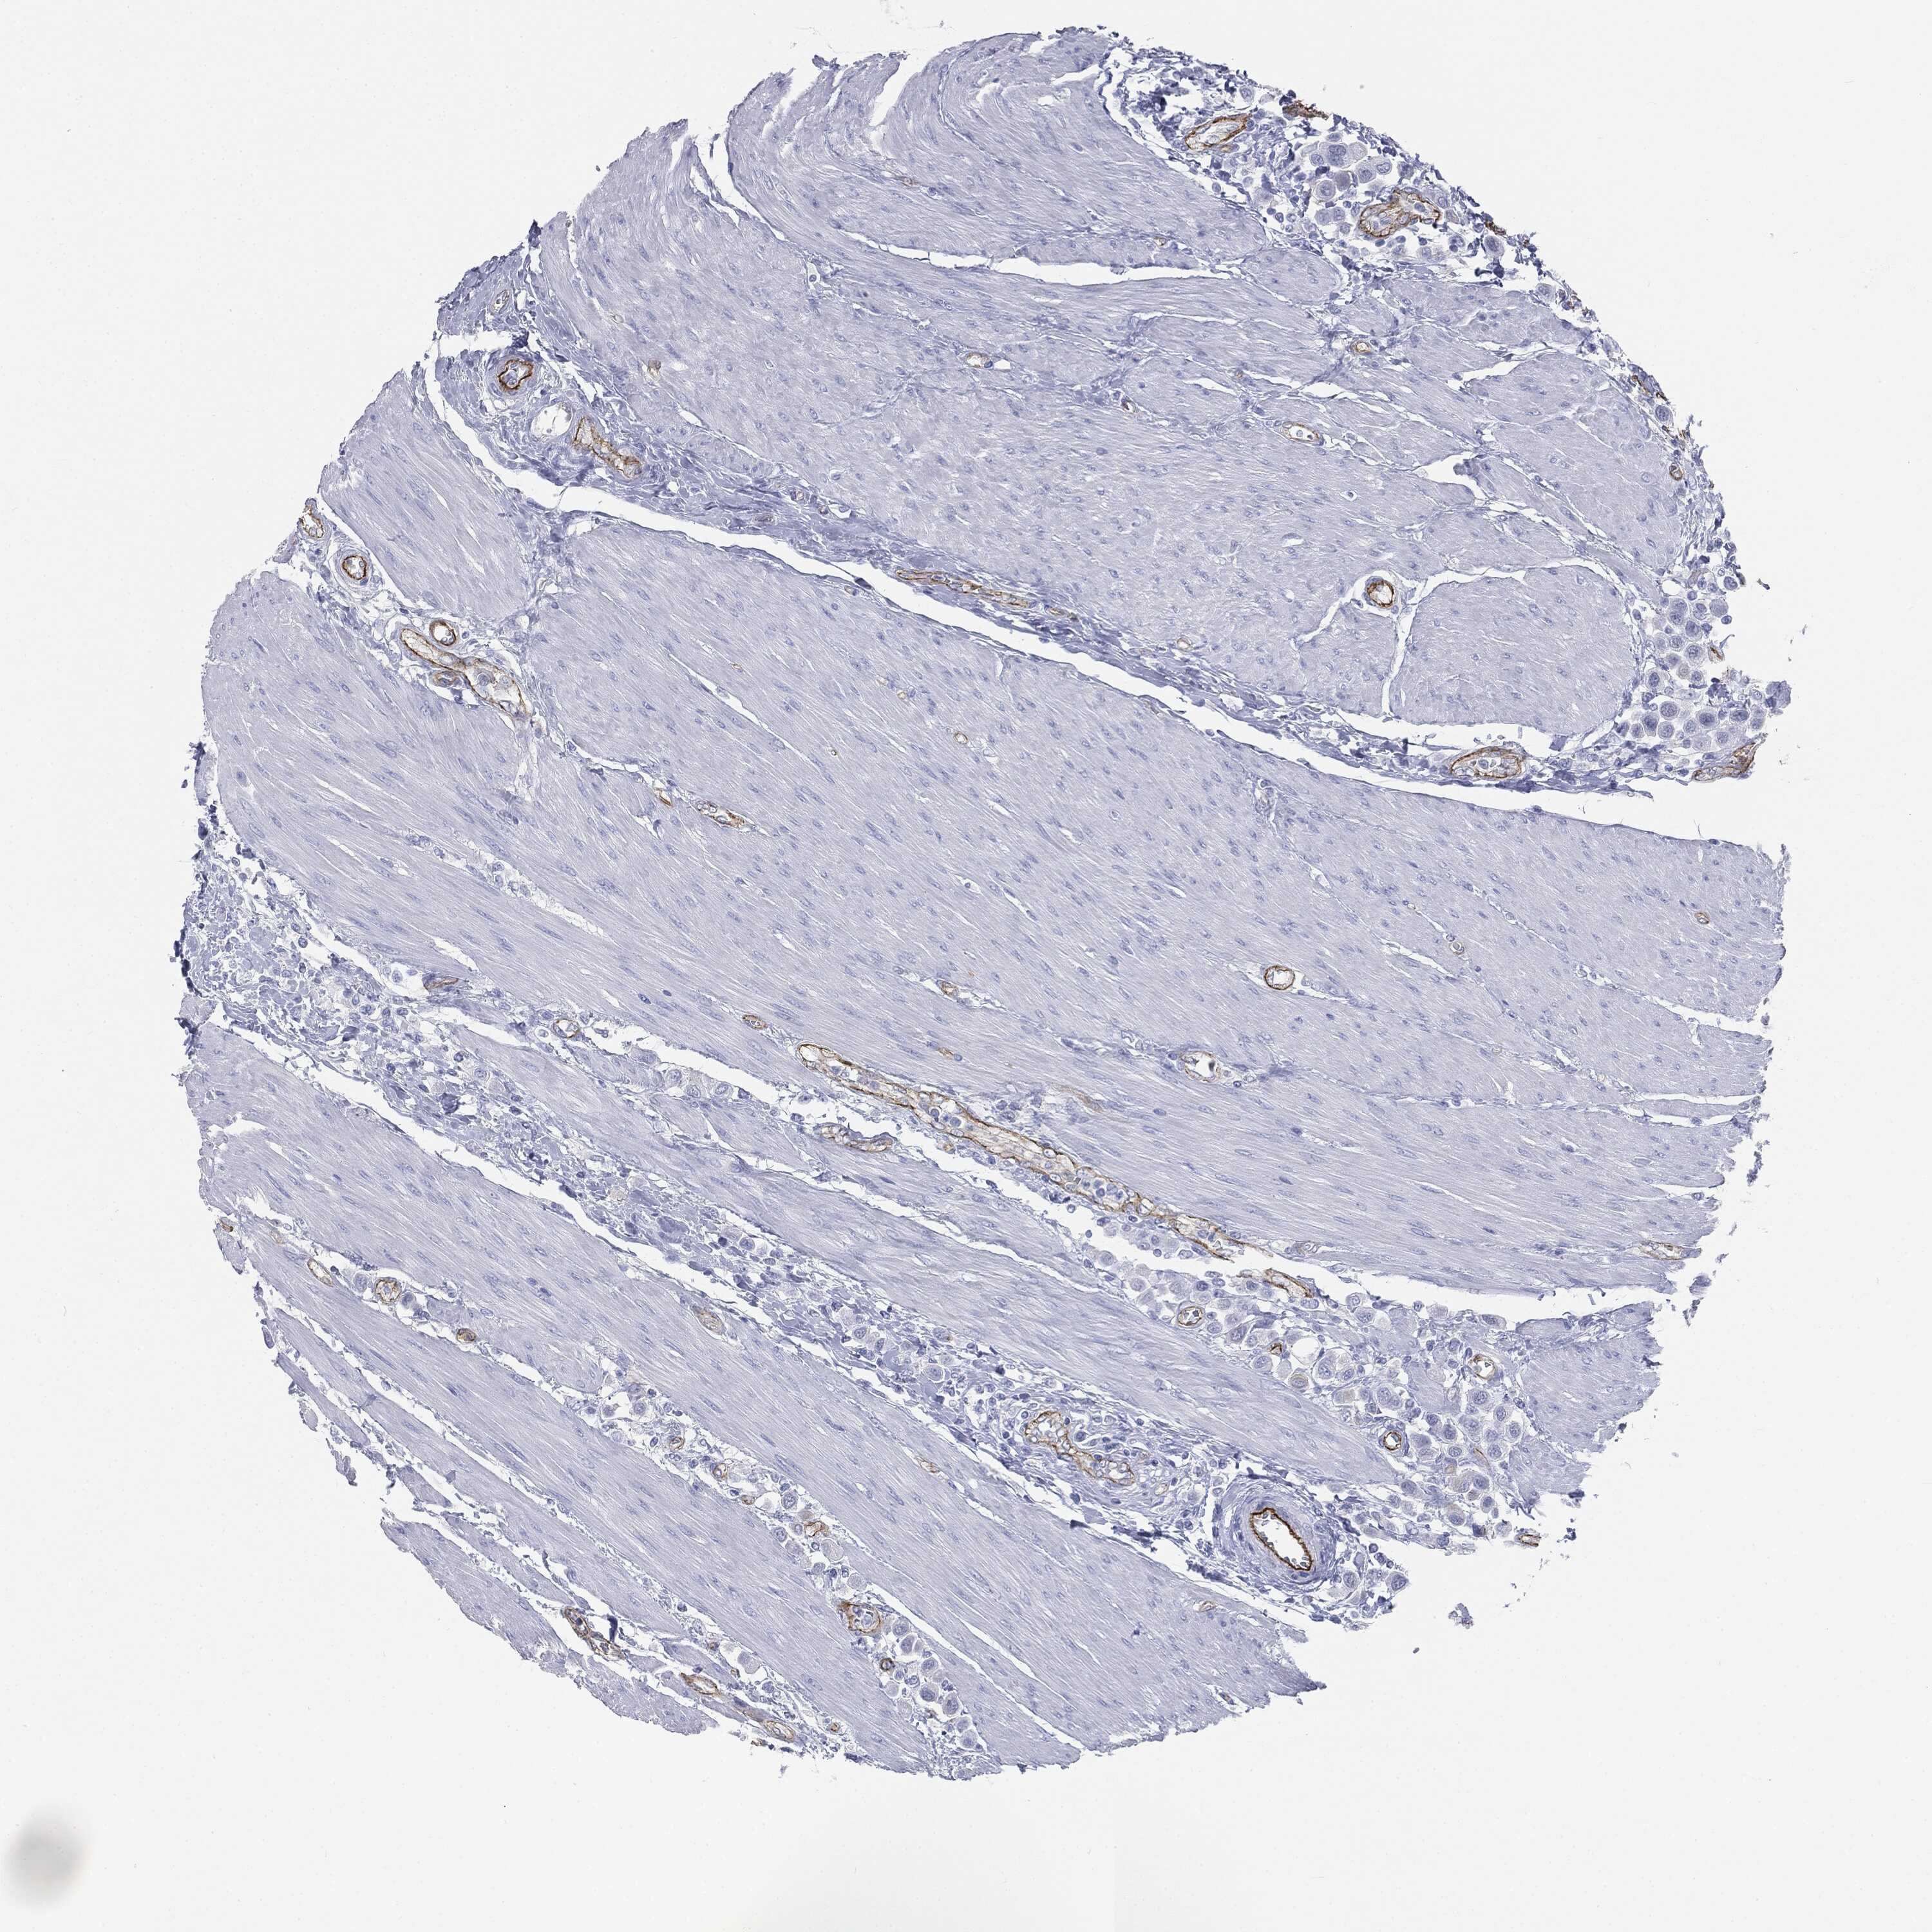

UROTHELIAL CANCER - Protein expressioni

A mouse-over function shows sample information and annotation data. Click on an image to view it in a full screen mode. Samples can be filtered based on level of antibody staining by selecting one or several of the following categories: high, medium, low and not detected. The assay and annotation is described here.

Note that samples used for immunohistochemistry by the Human Protein Atlas do not correspond to samples in the TCGA dataset.

Antibody stainingi

Antibody staining in the annotated cell types in the current human tissue is reported as not detected, low, medium, or high, based on conventional immunohistochemistry profiling in selected tissues. This score is based on the combination of the staining intensity and fraction of stained cells.

Each image is clickable and will lead to virtual microscopy that enables deeper exploration of all samples and also displays staining intensity scores, fraction scores and subcellular localization as well as patient and tissue information for each sample.

Urothelial carcinoma, High grade

Urothelial carcinoma, NOS

Urothelial carcinoma, Low grade

Adenocarcinoma, NOS